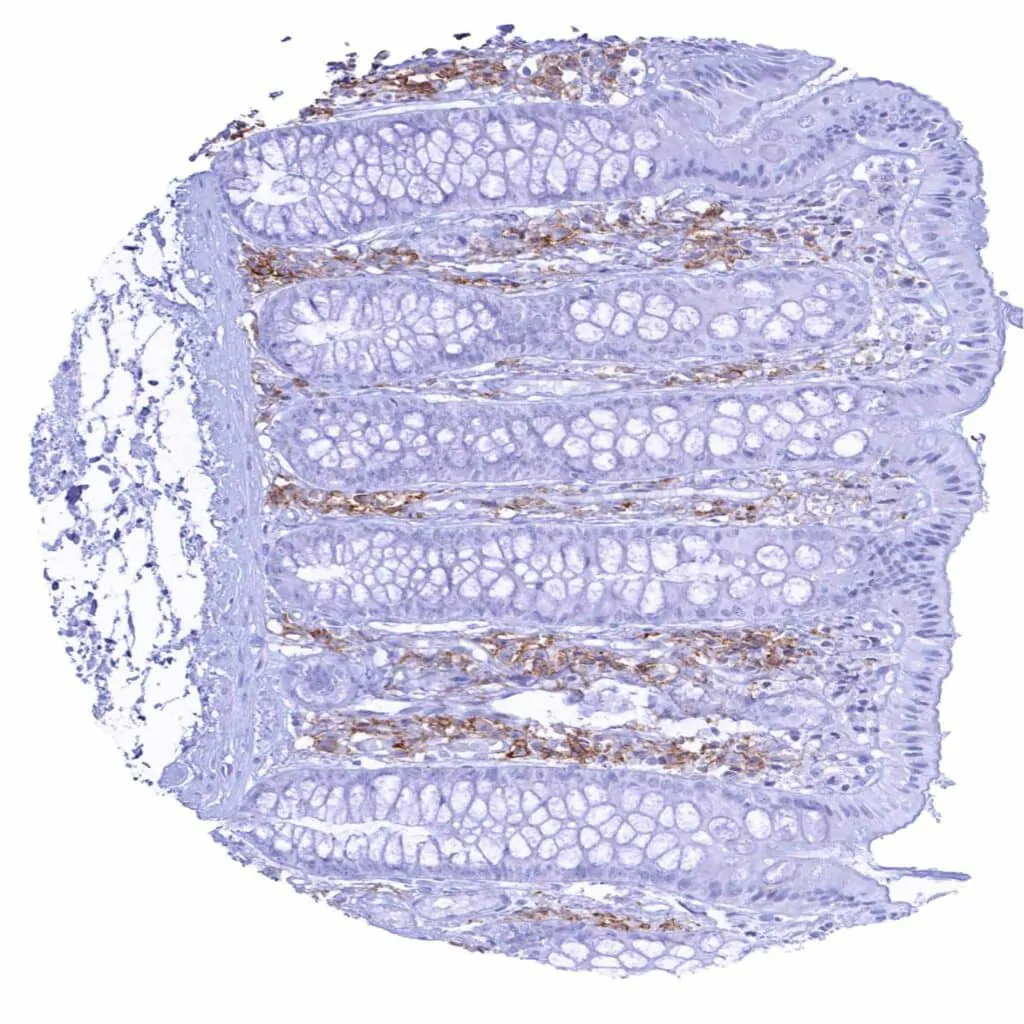

Appendix, mucosa – Strong CD38 staining of a subset of inflammatory cells

Appendix, mucosa